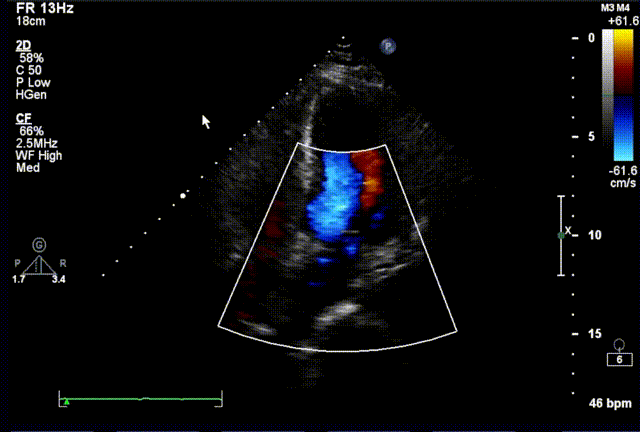

术后超声